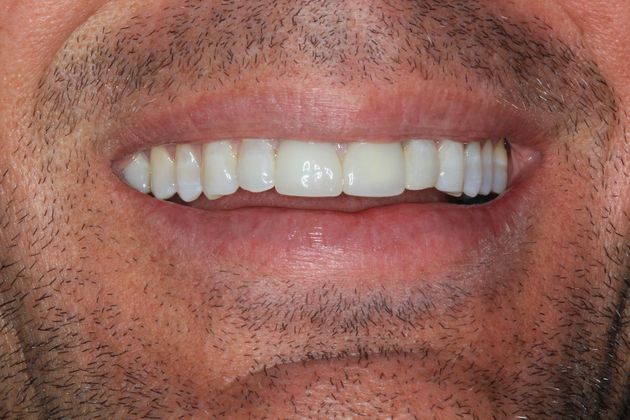

Full Mouth Reconstruction: Case 20

Description

This patient presented with old discolored crowns on his front two teeth, that were starting to break down. They had a metal substructure that he did not like the esthetics of. He is very happy with his new smile!